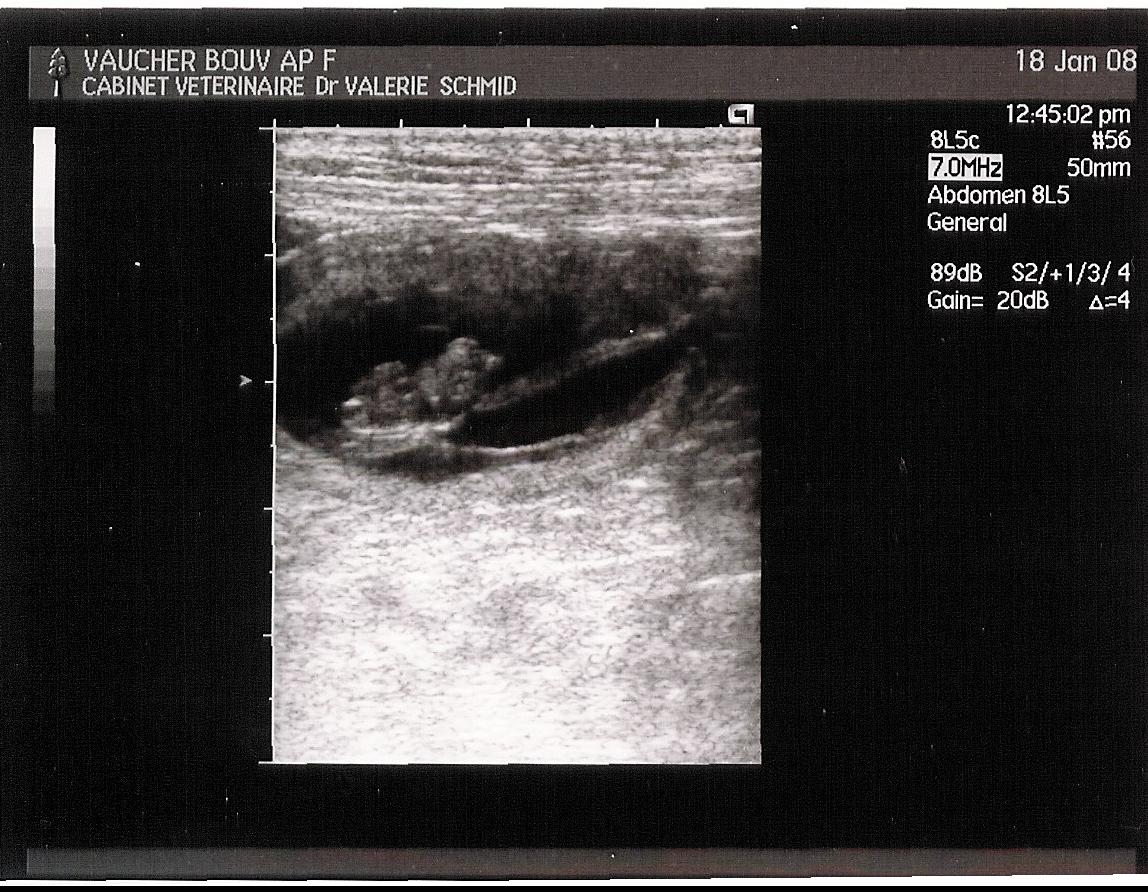

De cette aventure sont nés 2 femelles et 4 mâles, le 22 février 2008.